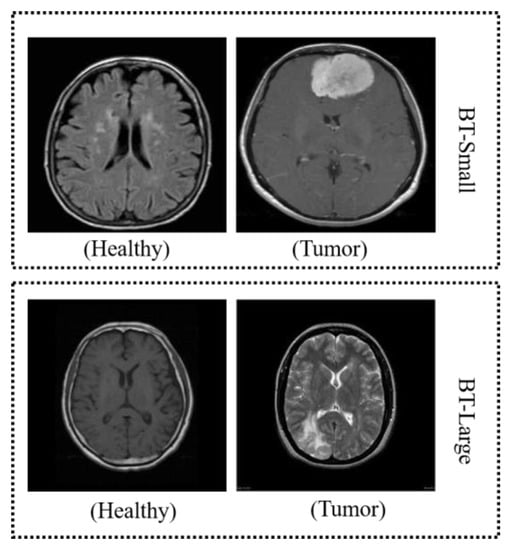

4.1. Dataset

| Study I | BT-small | 177 | 76 |

| Study II | BT-large | 2100 | 900 |